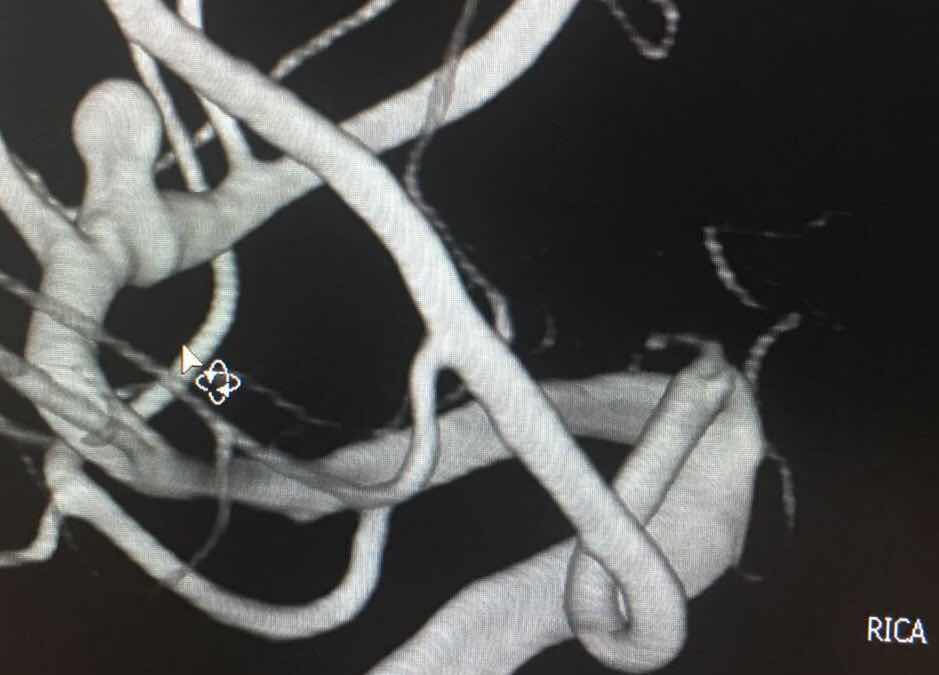

术前头部DSA

颅内动脉瘤被称为颅内的“不定时炸弹”,随时有再次破裂出血可能,一旦出血预后极差。患者属于亨-汉氏分级3级,急诊全脑脑血管造影显示患者为颅内多发动脉瘤,一枚位于右侧大脑中动脉M3段,一枚位于左侧大脑前动脉A1段。两枚动脉瘤相当于两枚“不定时炸弹”,其危险程度可想而知,而且术前难以判断责任动脉瘤。

开颅动脉瘤夹闭术已是神经外二科的常规手术,颅内多发动脉瘤位于同侧的已经开展了多例,但是两枚动脉瘤分别位于两侧尚属罕见,手术入路的选择尤为重要,一次夹闭双侧颅内动脉瘤难度加大,术前吴卫东主任带领神经外二科全体医生反复观阅脑血管选择性造影,结合头CT表现,最后得出右侧大脑中动脉动脉瘤可能为责任动脉瘤,手术入路选择为右侧翼点入路,那么左侧的动脉瘤能否顺利的夹闭就成了问题,如果只夹闭右侧动脉瘤,左侧也随时有破裂风险,危及患者生命,如果待患者恢复后再次手术治疗左侧动脉瘤无疑会增加患者的经济负担及承受再次开颅的创伤,本例患者处理左侧动脉瘤的难度是距离远,中间要跨越多处血管及神经,对于术者是一次严峻的考验。